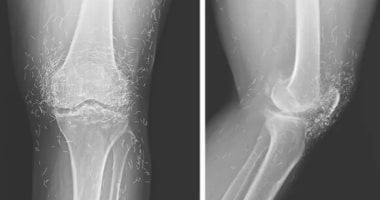

كشفت الأشعة السينية لامرأة من كوريا الجنوبية تبلغ من العمر 65 عامًا وجود مئات الخيوط الذهبية الدقيقة داخل مفاصل ركبتها، وذلك بعد أن قصدت المستشفى تشكو آلامًا حادة ومتكررة في الركبة.

لاحظ الأطباء في الأشعة وجود مئات النقاط الصغيرة اللامعة حول مفصل الركبة، وتبين لاحقًا أنها بقايا خيوط ذهبية، كما أظهرت الصور زيادة في سماكة العظام ونمو نتوءات عظمية بجانب المفصل، وهي علامات تقدم التهاب المفاصل.

يشير الأطباء أيضًا إلى أن وجود هذه الخيوط قد يعوق التشخيص الدقيق، إذ تترك ظلالًا على صور الأشعة وتكون خطرًا عند الخضوع لتصوير بالرنين المغناطيسي بسبب احتمالية تفاعلها مع المجالات المغناطيسية القوية وما قد ينتج عن ذلك من مخاطر صحية.